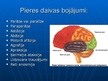

Smadzeņu pakauša, deniņu, paura un pieres daļas bojājumu neiropsiholoģiskie s...